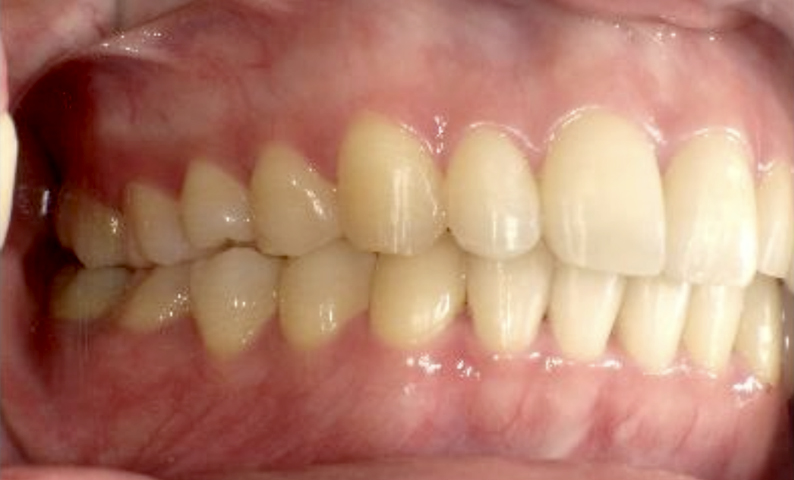

症例_025 上下顎の部分矯正

治療期間:13ヶ月金額:51万円+税女性前歯のガタガタ出っ歯

| Before | After |

|---|---|